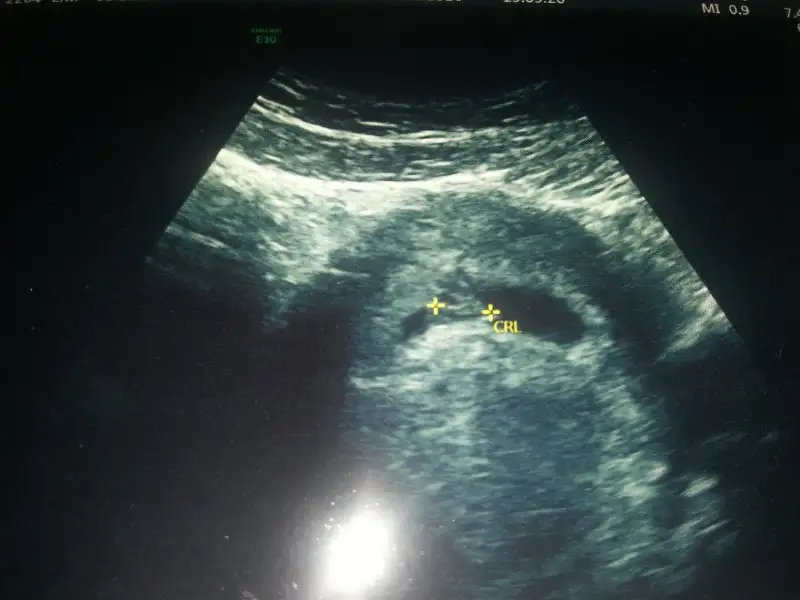

Arkadaslar benim bebeğim 7+3 haftasında ortada duruyor sizce cinsiyeti nedir?? Tahminde bulunursanız sevinirim :KK76:

16,7 KB · Görüntüleme: 89